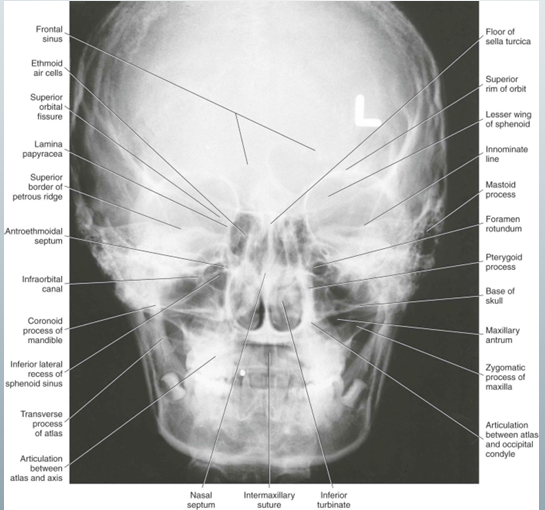

posteroanterior cephalometric

-”PA ceph”

-ortho uses to evaluate facial asymmetry

PA ceph uses, image receptor placement, pt position, central x-ray beam position, difference from PA skull view

how to take PA ceph

-image receptor perpendicular to pt’s midsagittal plane and parallel to coronal plane

-pt faces image receptor and tilts head slightly upward so the canthomeatal line forms a 10 degree angle with the transverse plane

-central x-ray beam positioned centered over the bridge of the nose

-canthomeatal line: line between the lateral canthus and the external auditory meatus